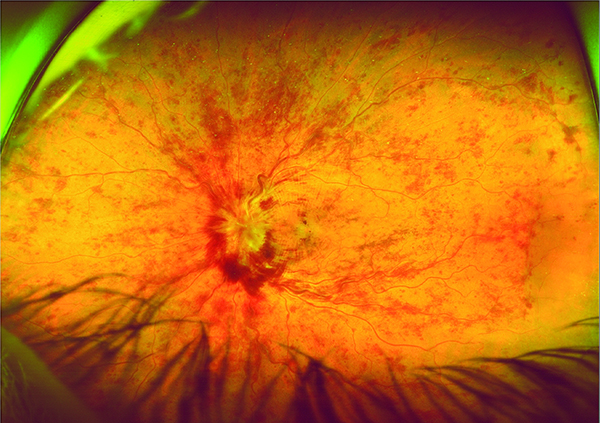

Fotografía panorámica